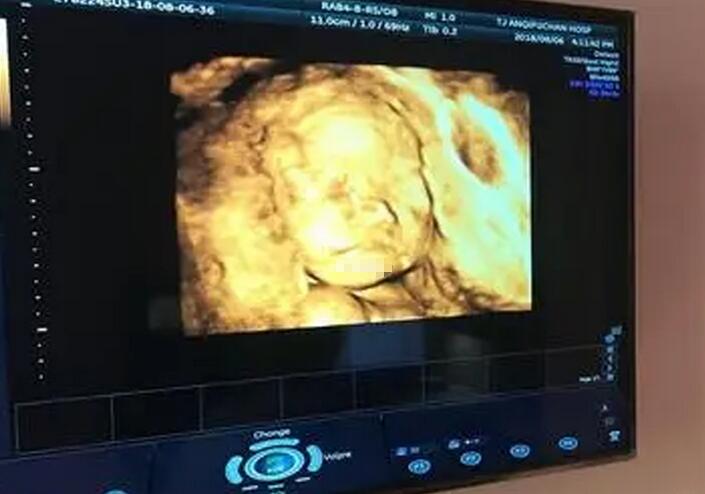

四维彩超是目前世界上最先进的彩色超声设备,它可以立体显示胎儿各部位的发育状况,帮助医生及早发现和诊断胎儿畸形,是孕期很重要的一项排畸检查。...[详细]

想必很多的孕妈妈都对四维彩超都是不陌生的,四维彩超不同于其他的超声检查...

孕期做四维彩超时,医生通过彩超可以清楚的观察到宝宝在肚子里发育的情况...

众所周知,孕妇做大排畸检查其实就是指四维彩超检查,可以清晰观察胎儿身体各部位生长发育情况的检查方法...

在孕期产检的众多项目中,四维彩超凭借能够立体呈现胎儿实时动态,排查多种胎儿发育畸形的优势...

四维彩色超声诊断仪是目前比较流行的产检技术,可以检测出胎儿大部分疾病,让孕妇能够全面了解宝宝的发育情况...